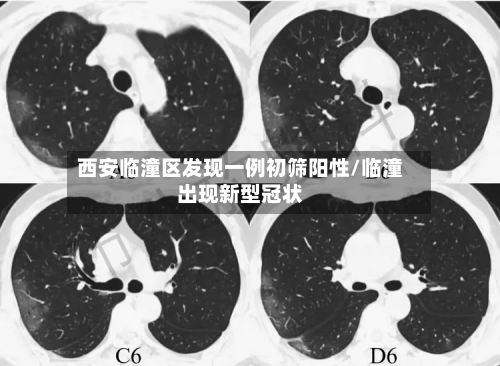

西安临潼区发现一例核酸初筛阳性人员,近来接触人员情况如何?

近来接触人员都已经按照规定报备,并且配合疫情防控的要求,接受隔离了。西安临潼区区发现一例核酸初筛阳性人员,近来已这名阳性人员有过间接性接触的人员基本上都已经按照当地的防疫规定向有关部门报备 ,并且配合相应的防疫措施,接受了隔离管控。

月18日,西安市临潼区在集中隔离人员中发现一例无症状感染者 。该病例曾于4月16日12:43至13:37在马额街道有活动轨迹 ,先后到马额街道旺盛达门业、鸿运建材商店购买建材等。

临潼区紧急寻人 4月18日,西安市临潼区在集中隔离人员中发现一例无症状感染者。该病例曾于4月16日12:43至13:37在马额街道有活动轨迹,先后到马额街道旺盛达门业、鸿运建材商店购买建材等。

〖壹〗、临潼区紧急寻人 4月18日 ,西安市临潼区在集中隔离人员中发现一例无症状感染者。该病例曾于4月16日12:43至13:37在马额街道有活动轨迹,先后到马额街道旺盛达门业 、鸿运建材商店购买建材等 。请4月16日以来去过马额街道的人员,立即就近向所在村委会(社区)或疫情防控部门进行报备,并落实从4月16日到21日5天3次核酸检测要求。